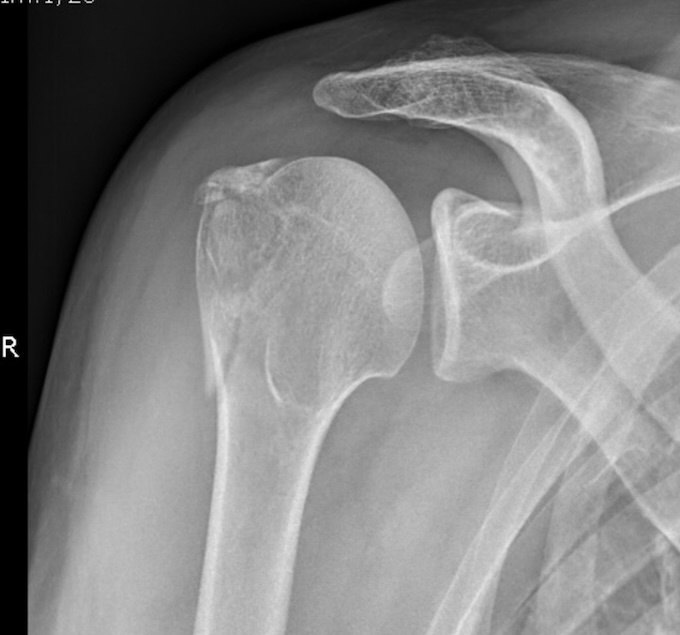

chinois02 | Sur un truc comme ça quand je bosse aux Urgences je demande l'avis chir ortho de suite. la partie osseuse fracturée est le siège d'insertions tendineuses et, à chaque fois que tu as mal à l'épaule, tu tires sur les bouts d'os cassé qui peuvent se déplacer et rendre l'intervention obligatoire secondairement!

Mais ton MT pourra immobiliser provisoirement la fracture. Message cité 1 fois Message édité par chinois02 le 10-04-2024 à 22:40:35 --------------- N'importe qui peut voir ce que tu sembles être; quelques rares seulement peuvent tâter ce que tu es. Et ces derniers n'osent contredire l'opinion du grand nombre, renforcée par toute la majesté de l'État. Machiavel-Le Prince. |